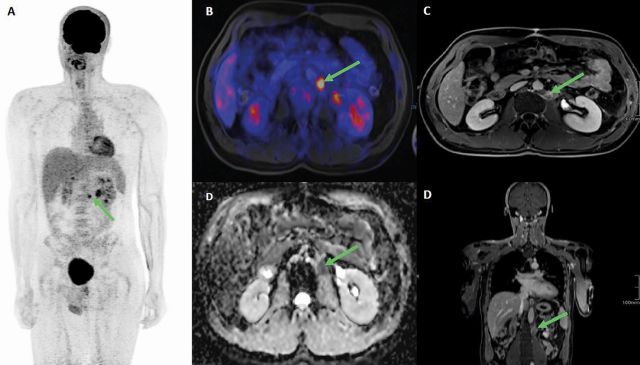

Die Herausforderungen bei der Bildgebung von Keimzelltumoren des Hodens